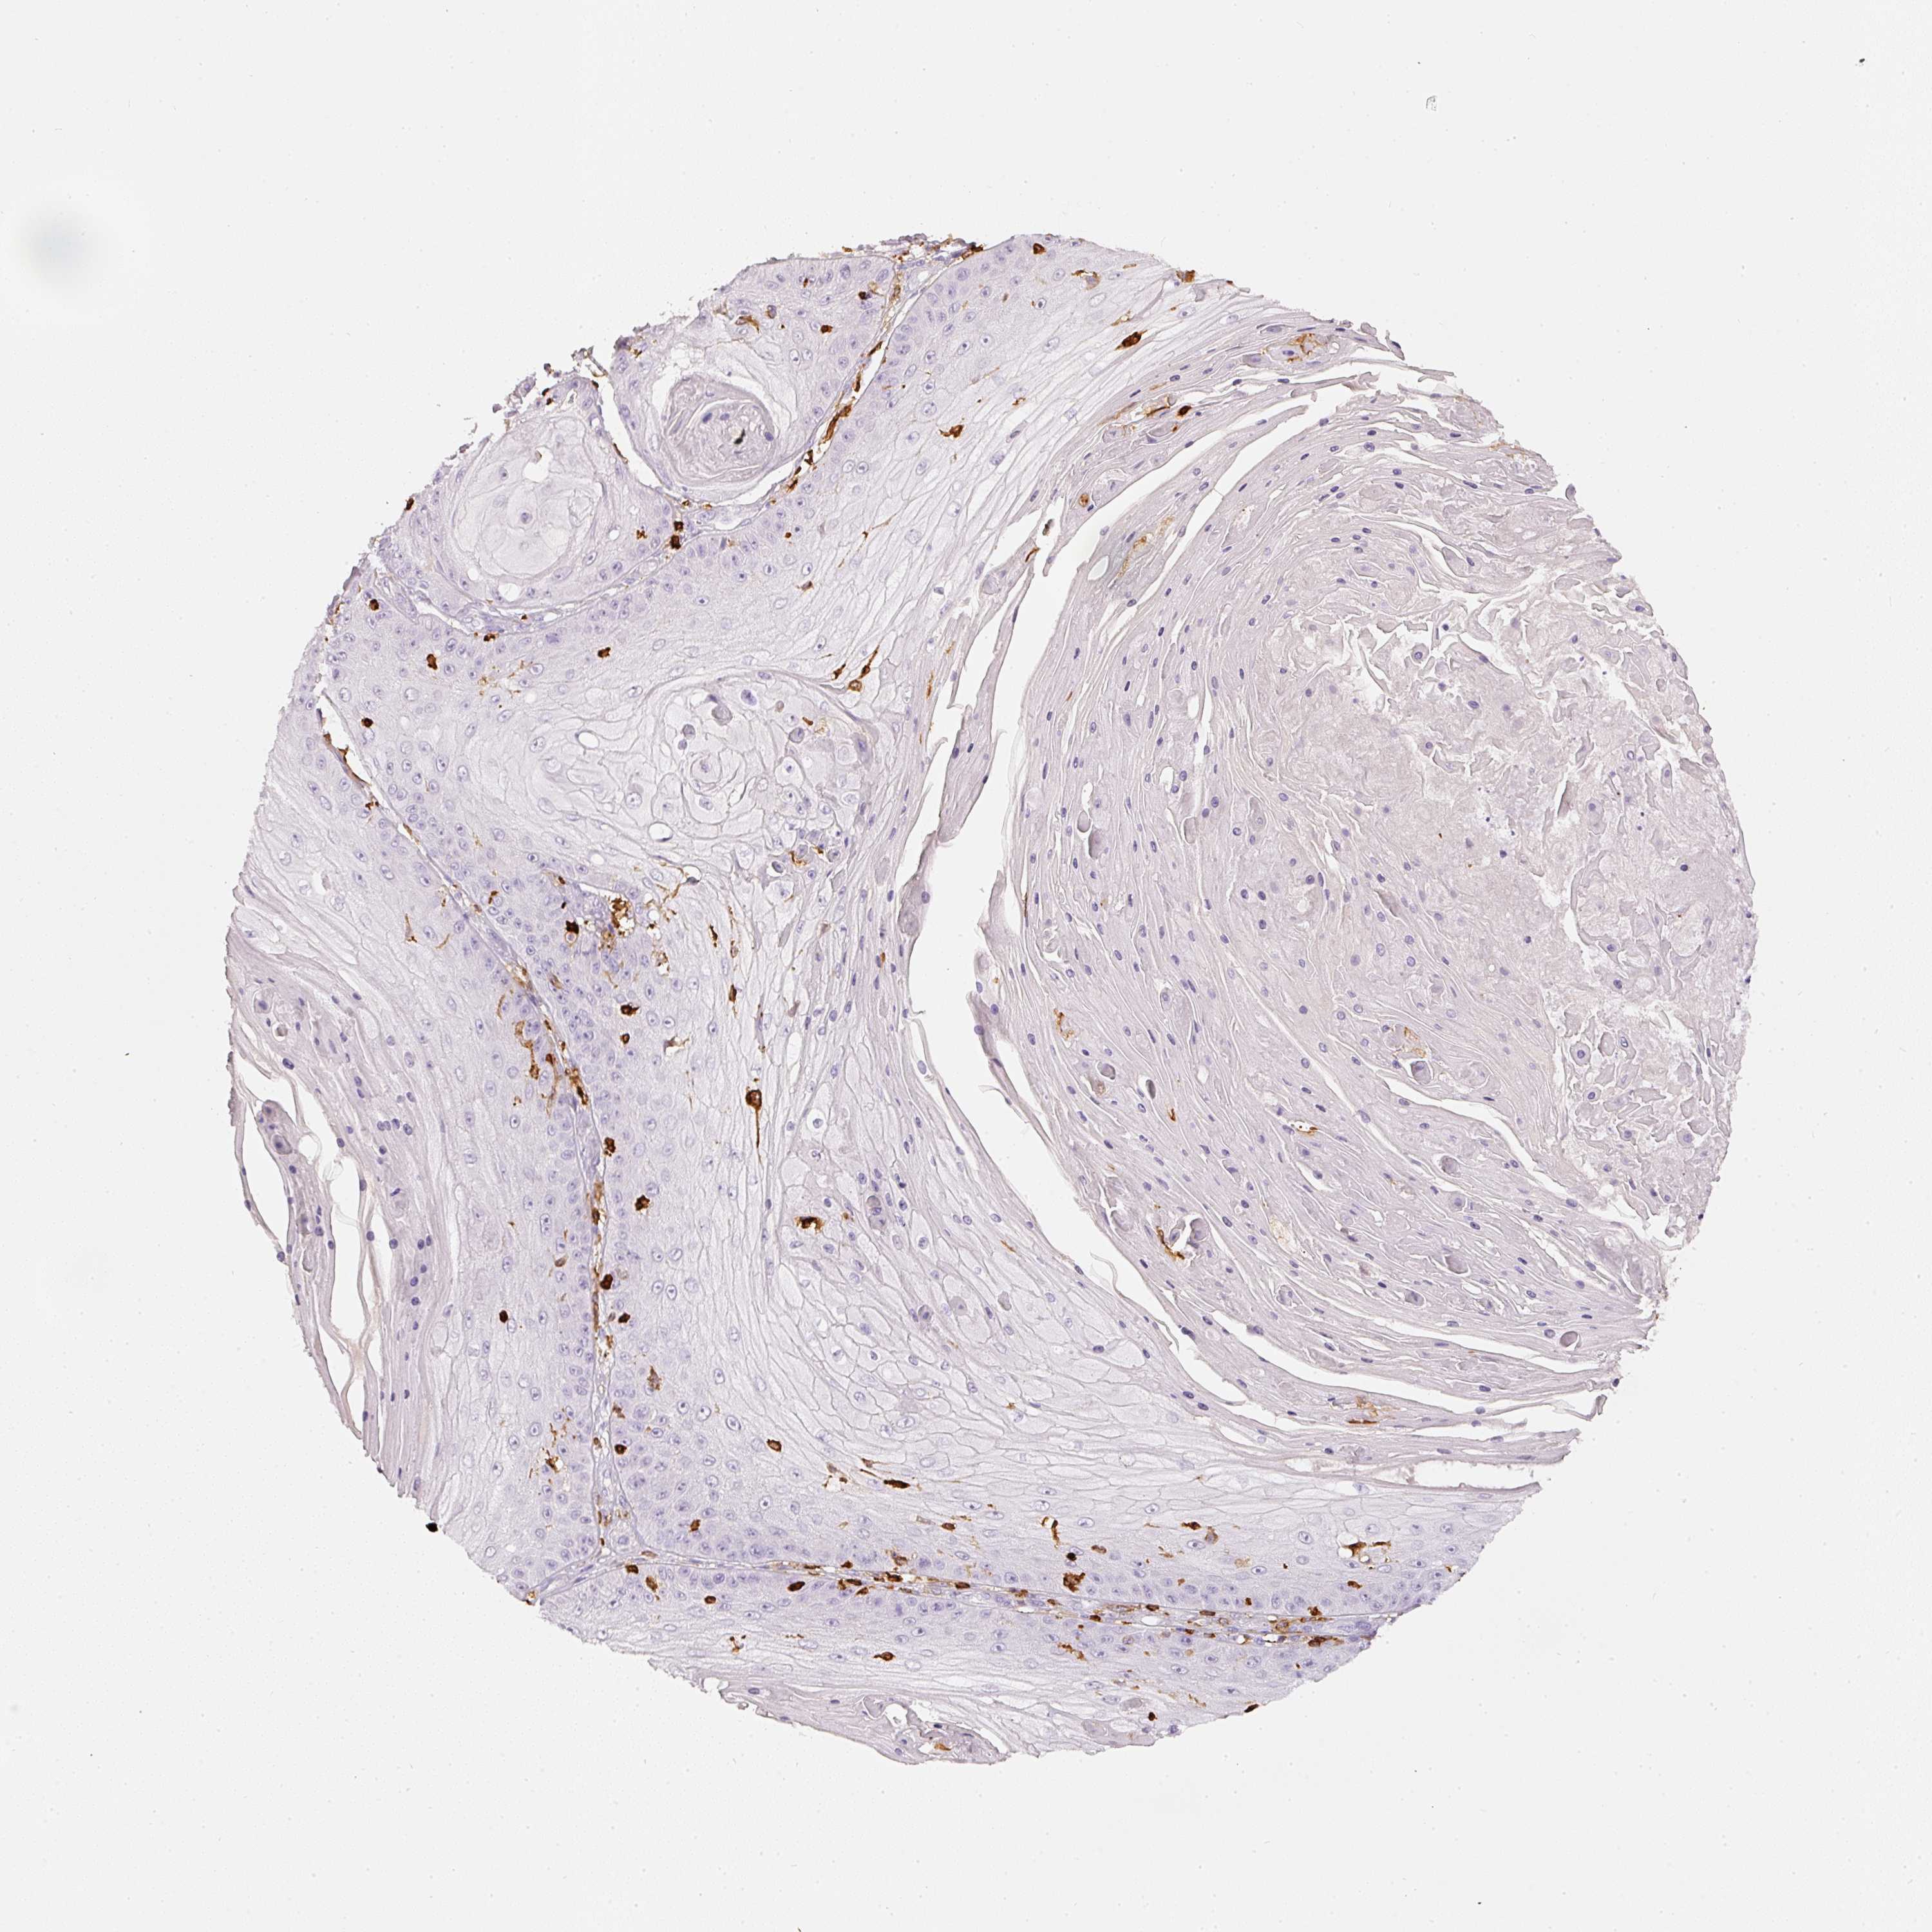

SKIN CANCER - Protein expressioni

A mouse-over function shows sample information and annotation data. Click on an image to view it in a full screen mode. Samples can be filtered based on level of antibody staining by selecting one or several of the following categories: high, medium, low and not detected. The assay and annotation is described here.

Each image is clickable and will lead to virtual microscopy that enables deeper exploration of all samples and also displays staining intensity scores, fraction scores and subcellular localization as well as patient and tissue information for each sample.

Antibody CAB033987

Squamous cell carcinoma, metastatic, NOS